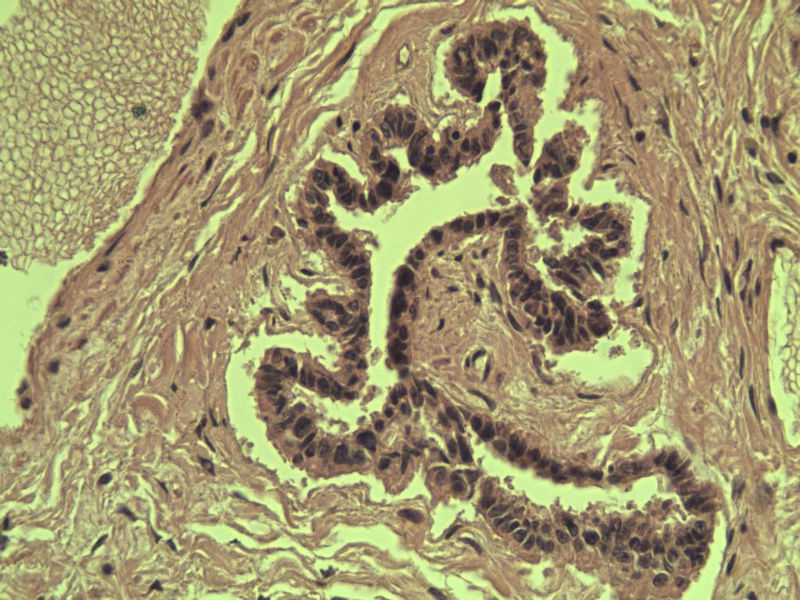

男 27岁 腹腔隐睾 5*3*2 cm, 切面灰红灰黄、实性、质中,请各位老师看看,是精原细胞瘤吗?感觉不像.腹腔隐睾图1

名称:图1

描述:a207.Jpg.jpg

精原细胞瘤

典型的精原细胞瘤,隐睾易恶变